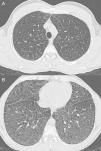

Case ReportA 40-year-old male diagnosed with N-P disease with hepatic and pulmonary affectation. Personal history included hepatosplenomegaly diagnosed at the age of 6–7 months. The patient was hospitalized at the age of 6 due to symptoms of asthenia, anorexia, deterioration and fever. Posteroanterior and lateral (PA-L) chest X-rays revealed diffuse reticular pattern. Given the radiographic findings and presence of hepatosplenomegaly, deposition disease was suspected. Rectal mucus and hepatic biopsies were suggestive of N-P disease (lipid-laden macrophages were observed). Neurological examination and respiratory function tests were normal. The diagnosis was confirmed when the patient was 20 using skin biopsy with fibroblast cultures, which confirmed a marked acid sphingomyelinase (ASM) deficiency characteristic of N-P disease that, supporting the clinical diagnosis, would be type B. At the age of 38, a molecular diagnosis revealed two mutations in the SMPD gene (heterozygosis in mutation p.R608del). The patient currently continues to be seen at the pulmonology and hepatology outpatient consultations, and he presents intermittent jaundice and maximal exertion dyspnea (MRC scale 0). On physical examination, minimal bibasilar crackles, subconjunctival jaundice and hepatosplenomegaly are observed. Neurological examination is normal. In the work-up, the most noteworthy results are: total bilirubin 4.17mg/dl; GOT 38IU/l; GPT 45IU/l; total cholesterol 221mg/dl. Lung function tests show a normal ventilatory pattern (FVC 3.84 [87.7%]; FEV1 3.13 [86%]; FEV1/FVC 81.58%; TLC 5.26 [81.8%]) and a mild alteration in the gas exchange (DLCO 57.5%). Radiographic findings on PA-L chest X-ray (Fig. 1A and B) include diffuse reticular interstitial affectation observed in the pulmonary parenchyma, predominantly in the middle and lower fields. HRCT (Aquilion Toshiba, 64-detector) (Fig. 2A and B) demonstrated diffuse ground-glass affectation, although predominantly in the lower lobes with subpleural septal thickening in the peripheral and mediastinal pleura and scissurae. No mediastinal or hilar lymphadenopathies are observed. The patient currently follows no type of treatment and only presents pulmonary and hepatic affectation with no central nervous system affectation.

Type B does not seem to favor either of the sexes and it can become evident at any age, although it is most frequently seen before the age of 20.7 There is a chronic visceral affectation that develops slowly2 and presents a wide variability in the severity of the symptoms and the clinical findings.3 Hepatosplenomegaly is rather common, with splenic growth above all.1 Liver function is affected, with an increase in transaminases and bilirubin. Thrombocytopenia may appear, which could be secondary to infiltration of the bone marrow by N-P cells,8 and leucopenia may also be caused. Lung disease is frequent and in most patients alterations appear on chest radiographs or HRCT.1 The exact incidence of the lung affectation is difficult to determine, but it is rare in adults and more common in pediatric forms.9 N-P cells accumulate in the alveolar septa, bronchial walls and pleura, and they cause a restrictive pattern that progressively worsens, which may lead to respiratory failure1 with oxygen dependence and/or reduced tolerance to physical exercise.10 Respiratory function tests show the said restrictive pattern with an incapacity for gas exchange, and cycle ergometry is abnormal in half of the patients.3 The radiological findings are determined by the existence of reticulonodular pattern with thickening of the interlobular septa, ground glass opacities and sometimes millimetric nodules that may be calcified.2,8,10 Occasionally, the combination of these findings produces an HRCT image known as “crazy paving”, although these findings are not specific. The differential diagnosis of this pattern includes: pulmonary edema, pulmonary hemorrhage, lymphangitis, alveolar proteinosis, amyloidosis3 and non-specific interstitial pneumonia. Nevertheless, the association with hepatosplenomegaly should suggest deposition disease.2 There is a poor correlation between lung function tests and morphologic findings on HRCT, which implies that the interstitial changes do not always affect the gas exchange to a significant degree.3,10 Therefore, the presence of interstitial lung disease on the simple X-ray or HRCT is not necessarily a reliable indicator of the appearance of clinical symptoms or of the alteration in the respiratory function tests. For the study of the lung alterations in this disease, chest radiography as well as HRCT should be used.1 In our case, the lung affectation was demonstrated when the patient was 6 years old with the detection of a reticular pattern on simple chest radiograph, but to date the patient has not presented significant respiratory symptoms.

Our case presents the majority of the radiological lung findings described in the literature with the presence of crazy paving with apical-basal gradient. The respiratory function tests did not correlate with the morphological alterations observed on HRCT as the respiratory tests were practically normal. Therefore, we believe that although N-P disease is a rare disease that presents non-specific radiological alterations, these can support the initial diagnosis and its confirmation. When confronted with a lipid storage disorder or a deposition disease, lung affectation must always be contemplated, and the most reliable radiological technique is HRCT.5 Although the crazy paving pattern is not the most specific for this type of disease, it should be included in the differential diagnosis, in accordance with what has been previously stated in the literature.5,10